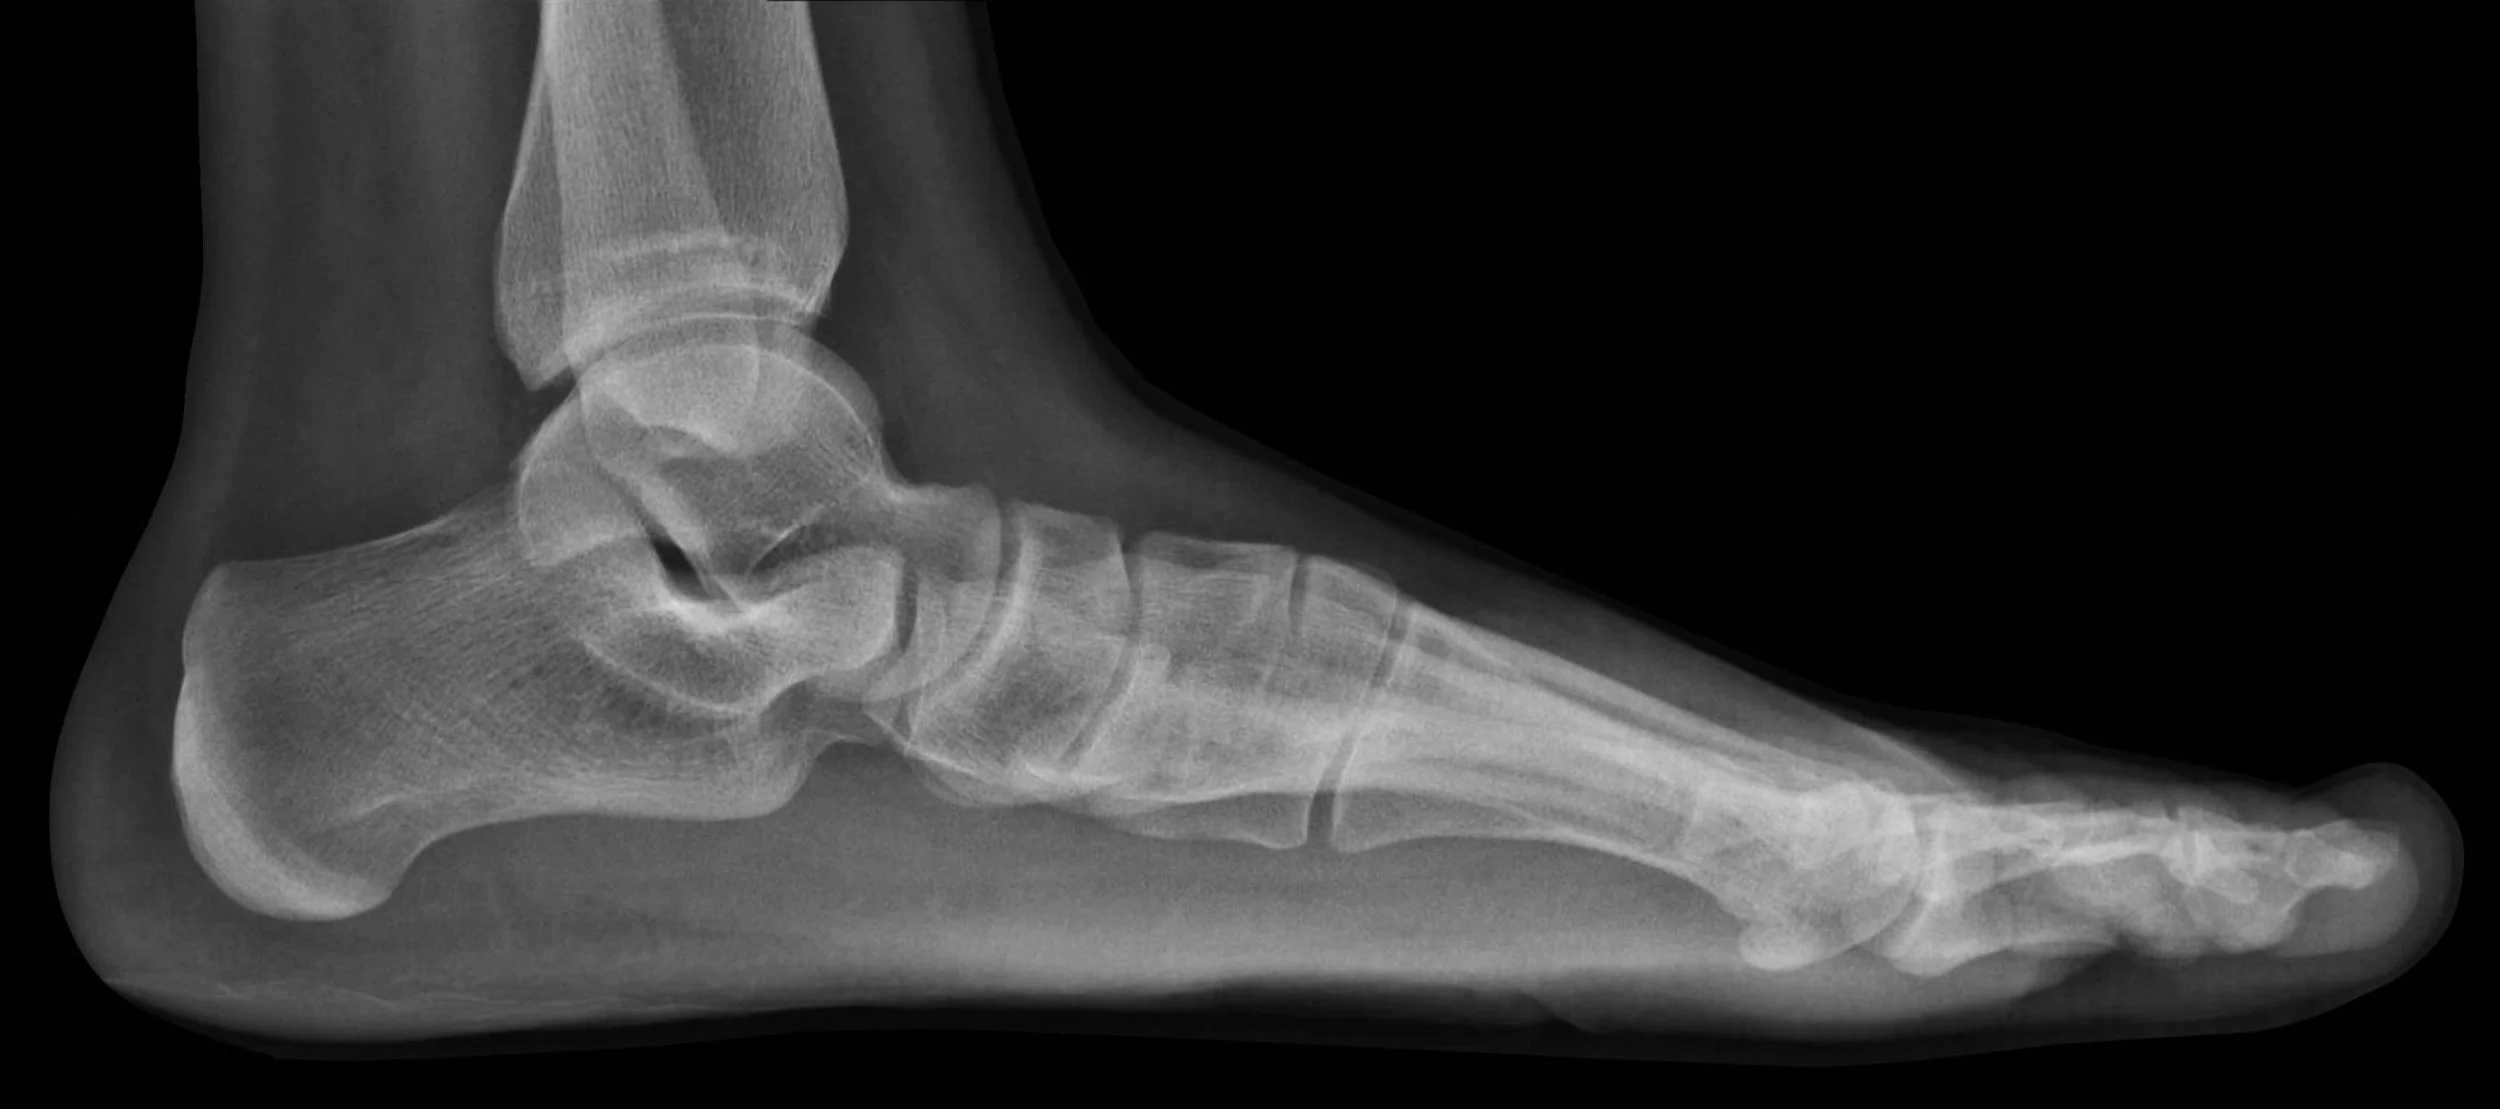

Posture functions to maintain alignment of the body’s segments in any position which is vital to not only normal walking but just about all our daily activities. Think about that. Now, what if I also told you that it's quite possible that your back pain, hip pain, knee pain, and even pain in your jaw may not be related to any one of those individual body parts at all? The real reason might simply be that you have a common postural deformity known as Flatfeet. Flatfeet cause pain in the lower body by putting a strain on the muscles, tendons, bones, and ligaments in the feet. Strain means they pull awkwardly on the muscles connected to the feet, which can throw someone's whole body out of alignment, thus causing pain in other areas.

Flatfeet cause the lower legs and thighs to roll inward, as a result, the kneecap moves out of its natural position and cannot stay in its natural groove in the thigh bone. This causes friction back and forth every time the leg is flexed or extended, which causes pain in the knee. If it moves up into the pelvic region, it can cause your pelvis to move forward, putting tension on your lower back and hamstring muscles. This in turn puts extra pressure on the discs which can develop into a painful condition called sciatica that causes radiating pain down into your legs. As we move up the body, your lower back turns in one direction and causes exaggerated bending in another direction in your upper back, putting pressure on your neck and causing your head to tilt forward on your neck giving you tightness in the jaw muscles as well as your neck muscles. Temporomandibular Joint Syndrome (TMJ) can also be caused by being extremely flatfooted.

While many people who have Flatfeet do not exhibit any outward signs or symptoms that indicate Flatfeet, some people may feel arch pain. More often than not, flatfeet cause noticeable fatigue in the arches, heels, knees, or lower back. Other common symptoms of Flatfeet include:

To find out if you have Flatfeet, there is a simple test you can do on your own—all you need is a concrete or cardboard surface and some water. Start by getting your feet wet, then stand normally on a flat surface. Then, step away from the imprints and evaluate the step marks. People with normal arches will see an imprint with the inside curve of the foot missing. People with Flatfeet will see the entire imprint of the bottom of the foot.